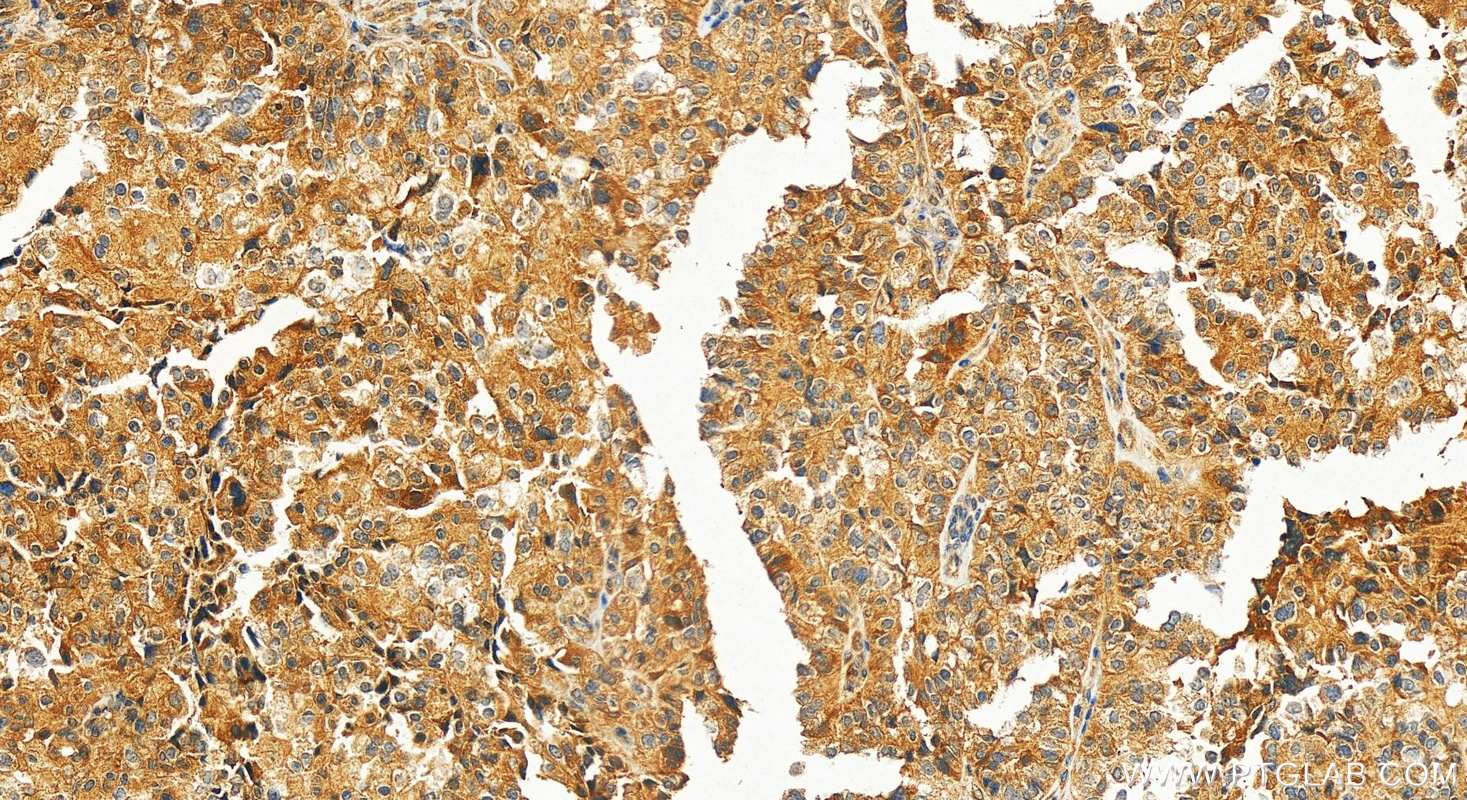

| Positive IHC detected in | human ovary cancer tissue Note: suggested antigen retrieval with TE buffer pH 9.0; (*) Alternatively, antigen retrieval may be performed with citrate buffer pH 6.0 |

| Immunohistochemistry (IHC) | IHC : 1:250-1:1000 |